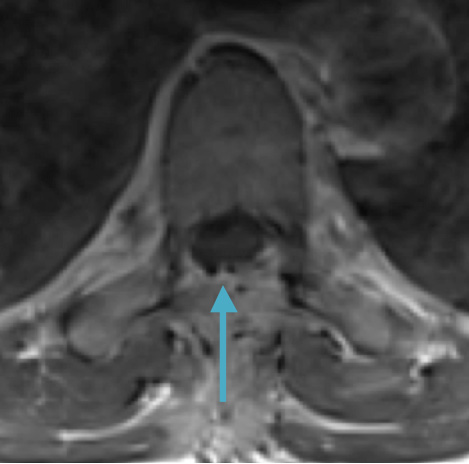

Preoperative MRI T2 demonstrating obstruction of CSF around the cord (blue arrow), resulting from the tumor (red arrow)

This is a 55-year-old female with no past medical history who presented electively with a 10 month history of progressively worsening mid back pain radiating across the chest, and gait disturbance. Pain was especially worse at night and when laying flat. Her exam was pertinent for severe ataxia when ambulating, and elevated deep tendon reflexes in the lower extremities. She had severe and debilitating symptoms, as demonstrated by her Visual Analog Scale (VAS) and Oswestry Disability Index (ODI) of 9/10 and 64/100, respectively. MRI of the thoracic spine with and without contrast demonstrated a large intradural extramedullary homogenously enhancing mass at T8, resulting in near obliteration of the spinal canal and severe cord compression. She was referred to Dr. Xavier Gaudin for neurosurgical management.